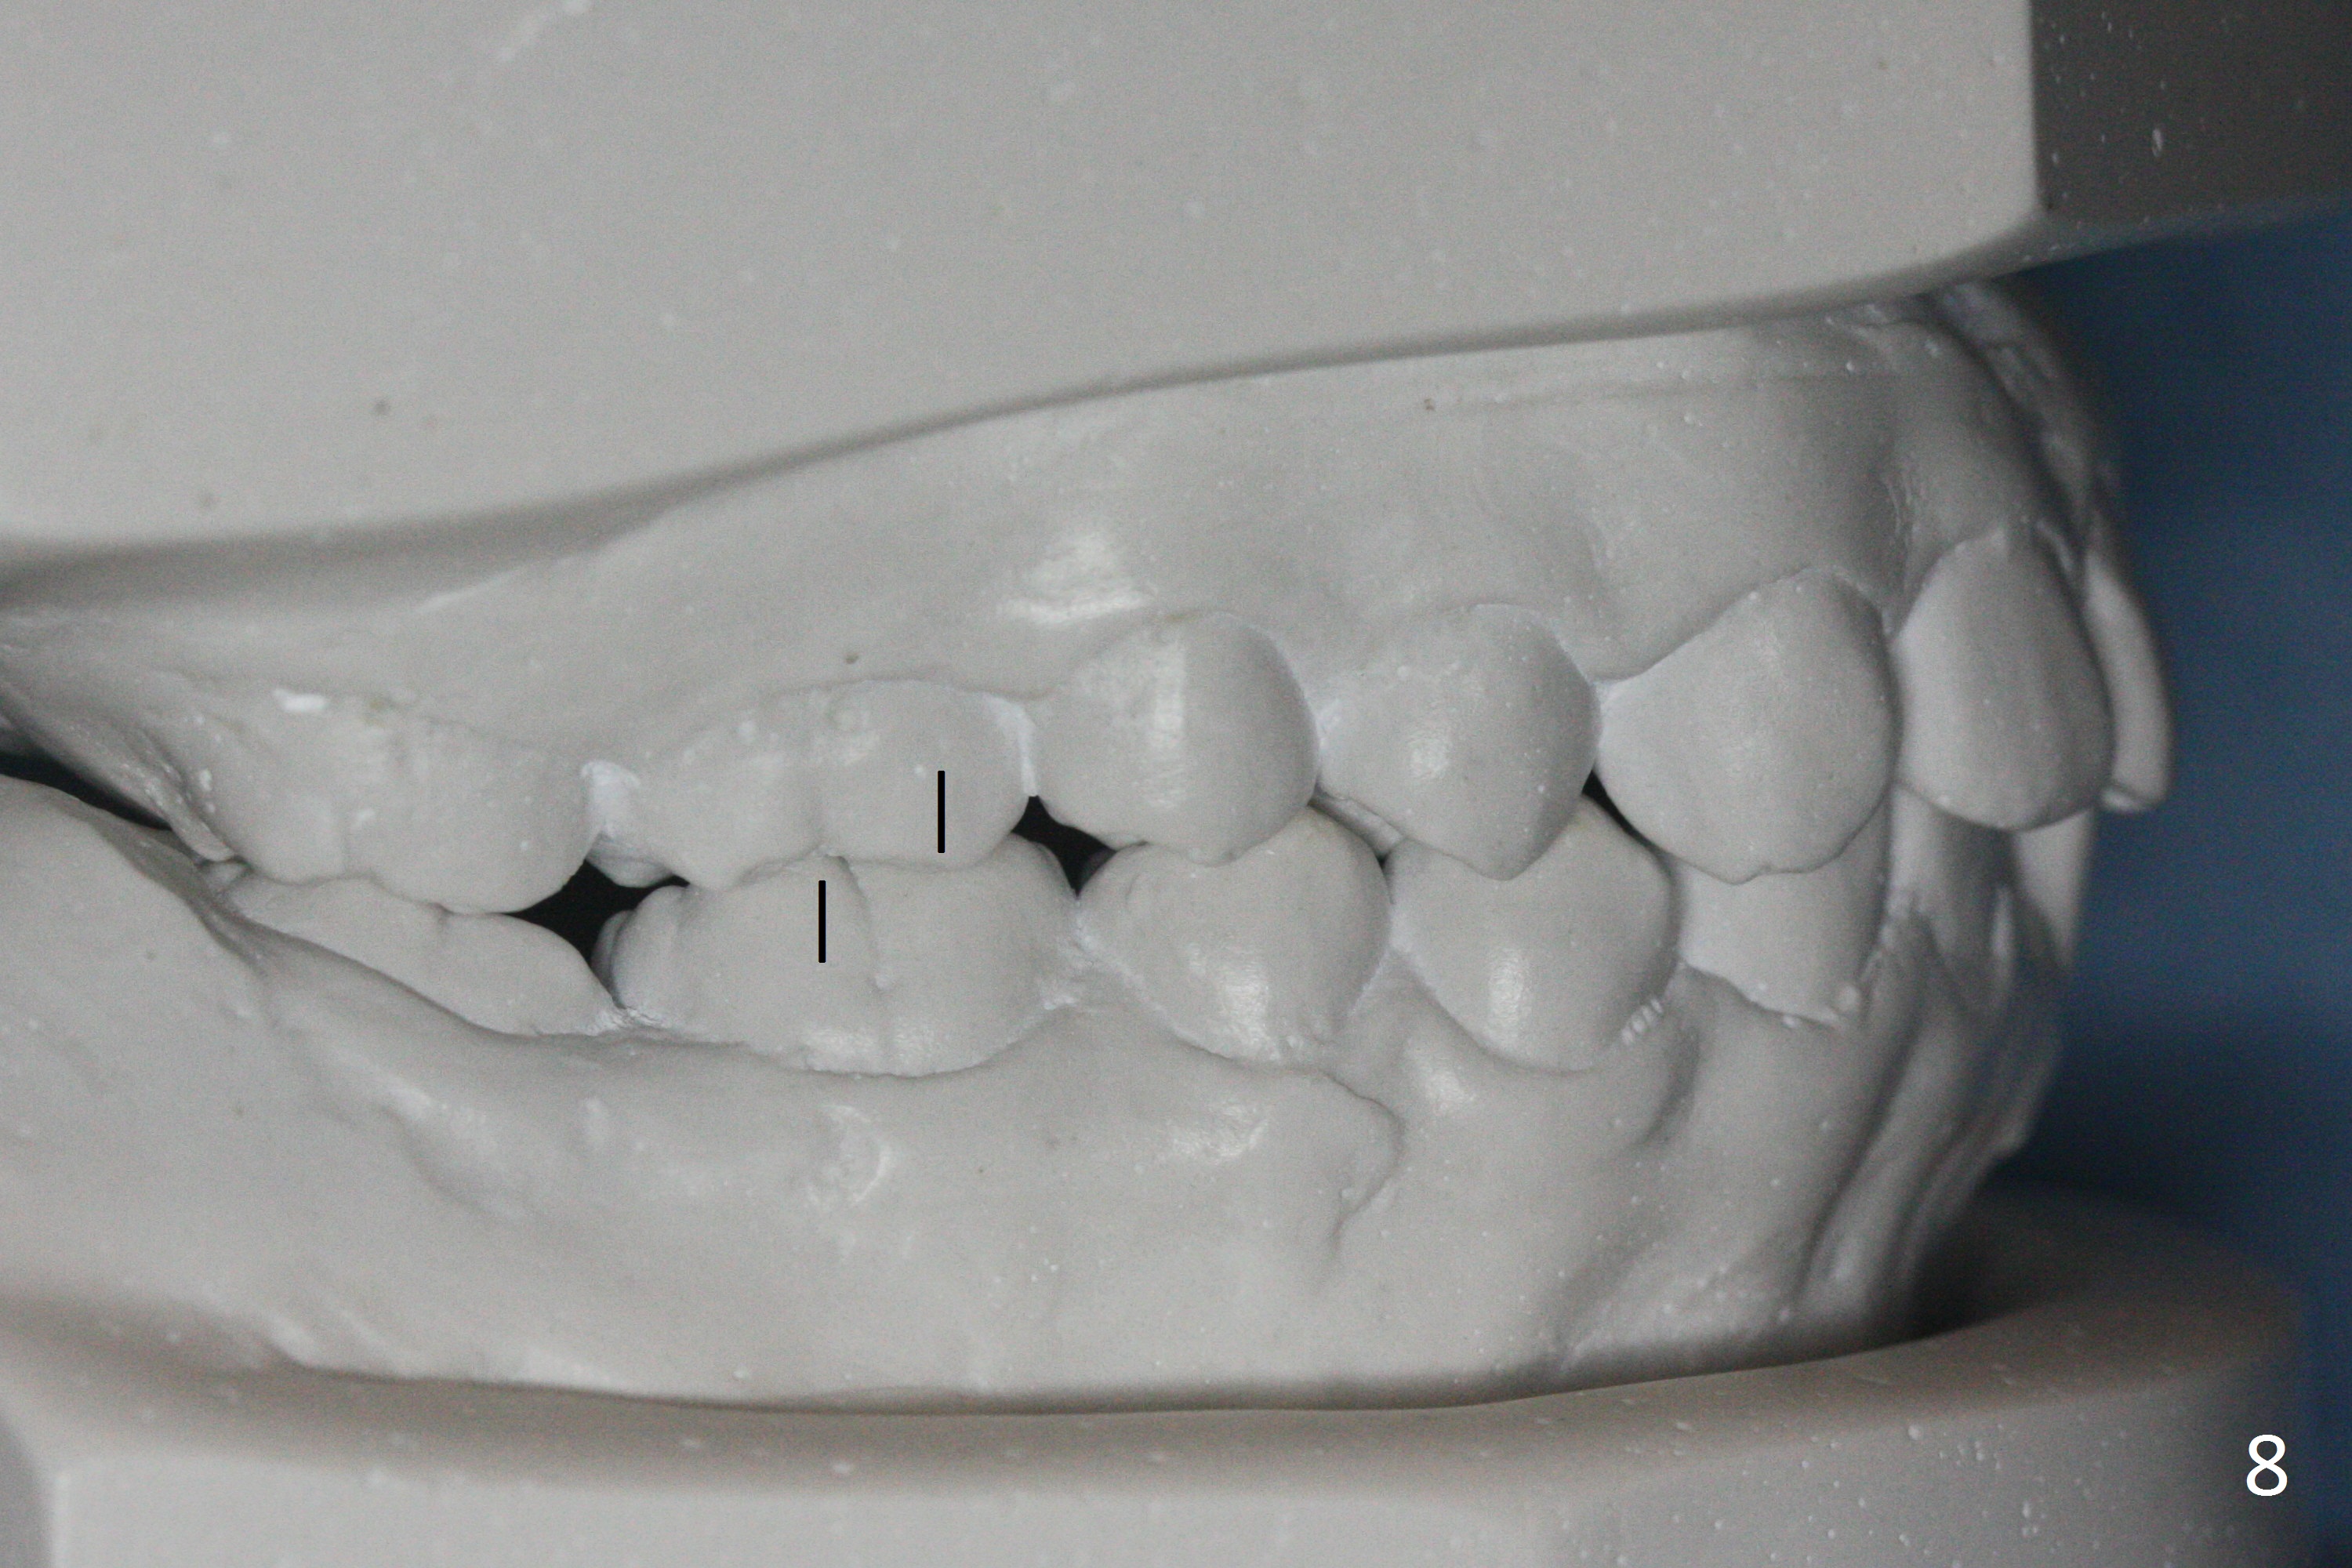

A 17-year-old woman will return for bracketing after caries control and deciduous tooth (Fig.6 arrowheads) extraction. Her profile is slightly protrusive (Fig.1,2). Crowding is more severe in the left posterior region (Fig.4) than the right one (Fig.3). The anterior crowding is also severe (Fig.5). Proximal reduction and use of power chain for constriction will be used instead of extraction of 4 bicuspids. Third molar extraction may have to be done prior to banding, especially for the lower right 2nd molar (Fig.7).

By looking at preop models (Fig.8-13), do you think whether extraction is a better option than non-extraction? Class II occlusion on the right (Fig.8), Class I on the left (Fig.10). With extraction of the 1st bicuspids, the posterior occlusion could be normal with further anterior protrusion (Fig.11). The upper arch is rounded (Fig.12); without extraction, the arch may turn out to be U-shaped. The lower arch is more crowded (Fig.13). Without space, the lower right 2nd molar may not be uprighted (Fig.7).